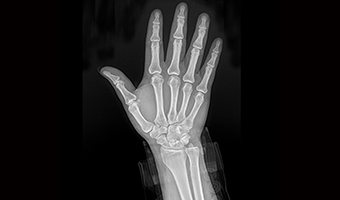

100µm Görüntüleme Teknolojisi

İnce veya gizli lezyonların gözlemlenmesine yardımcı olur

·2.4/5G Çift frekanslı kablosuz iletim

·17“X17“ Geniş Görüş Alanı

·%75 DQE Düşük doz

·100µm Piksel aralığı

·18 Milyon piksel

100μm Görüntüleme, İnce Detayları Hissetme